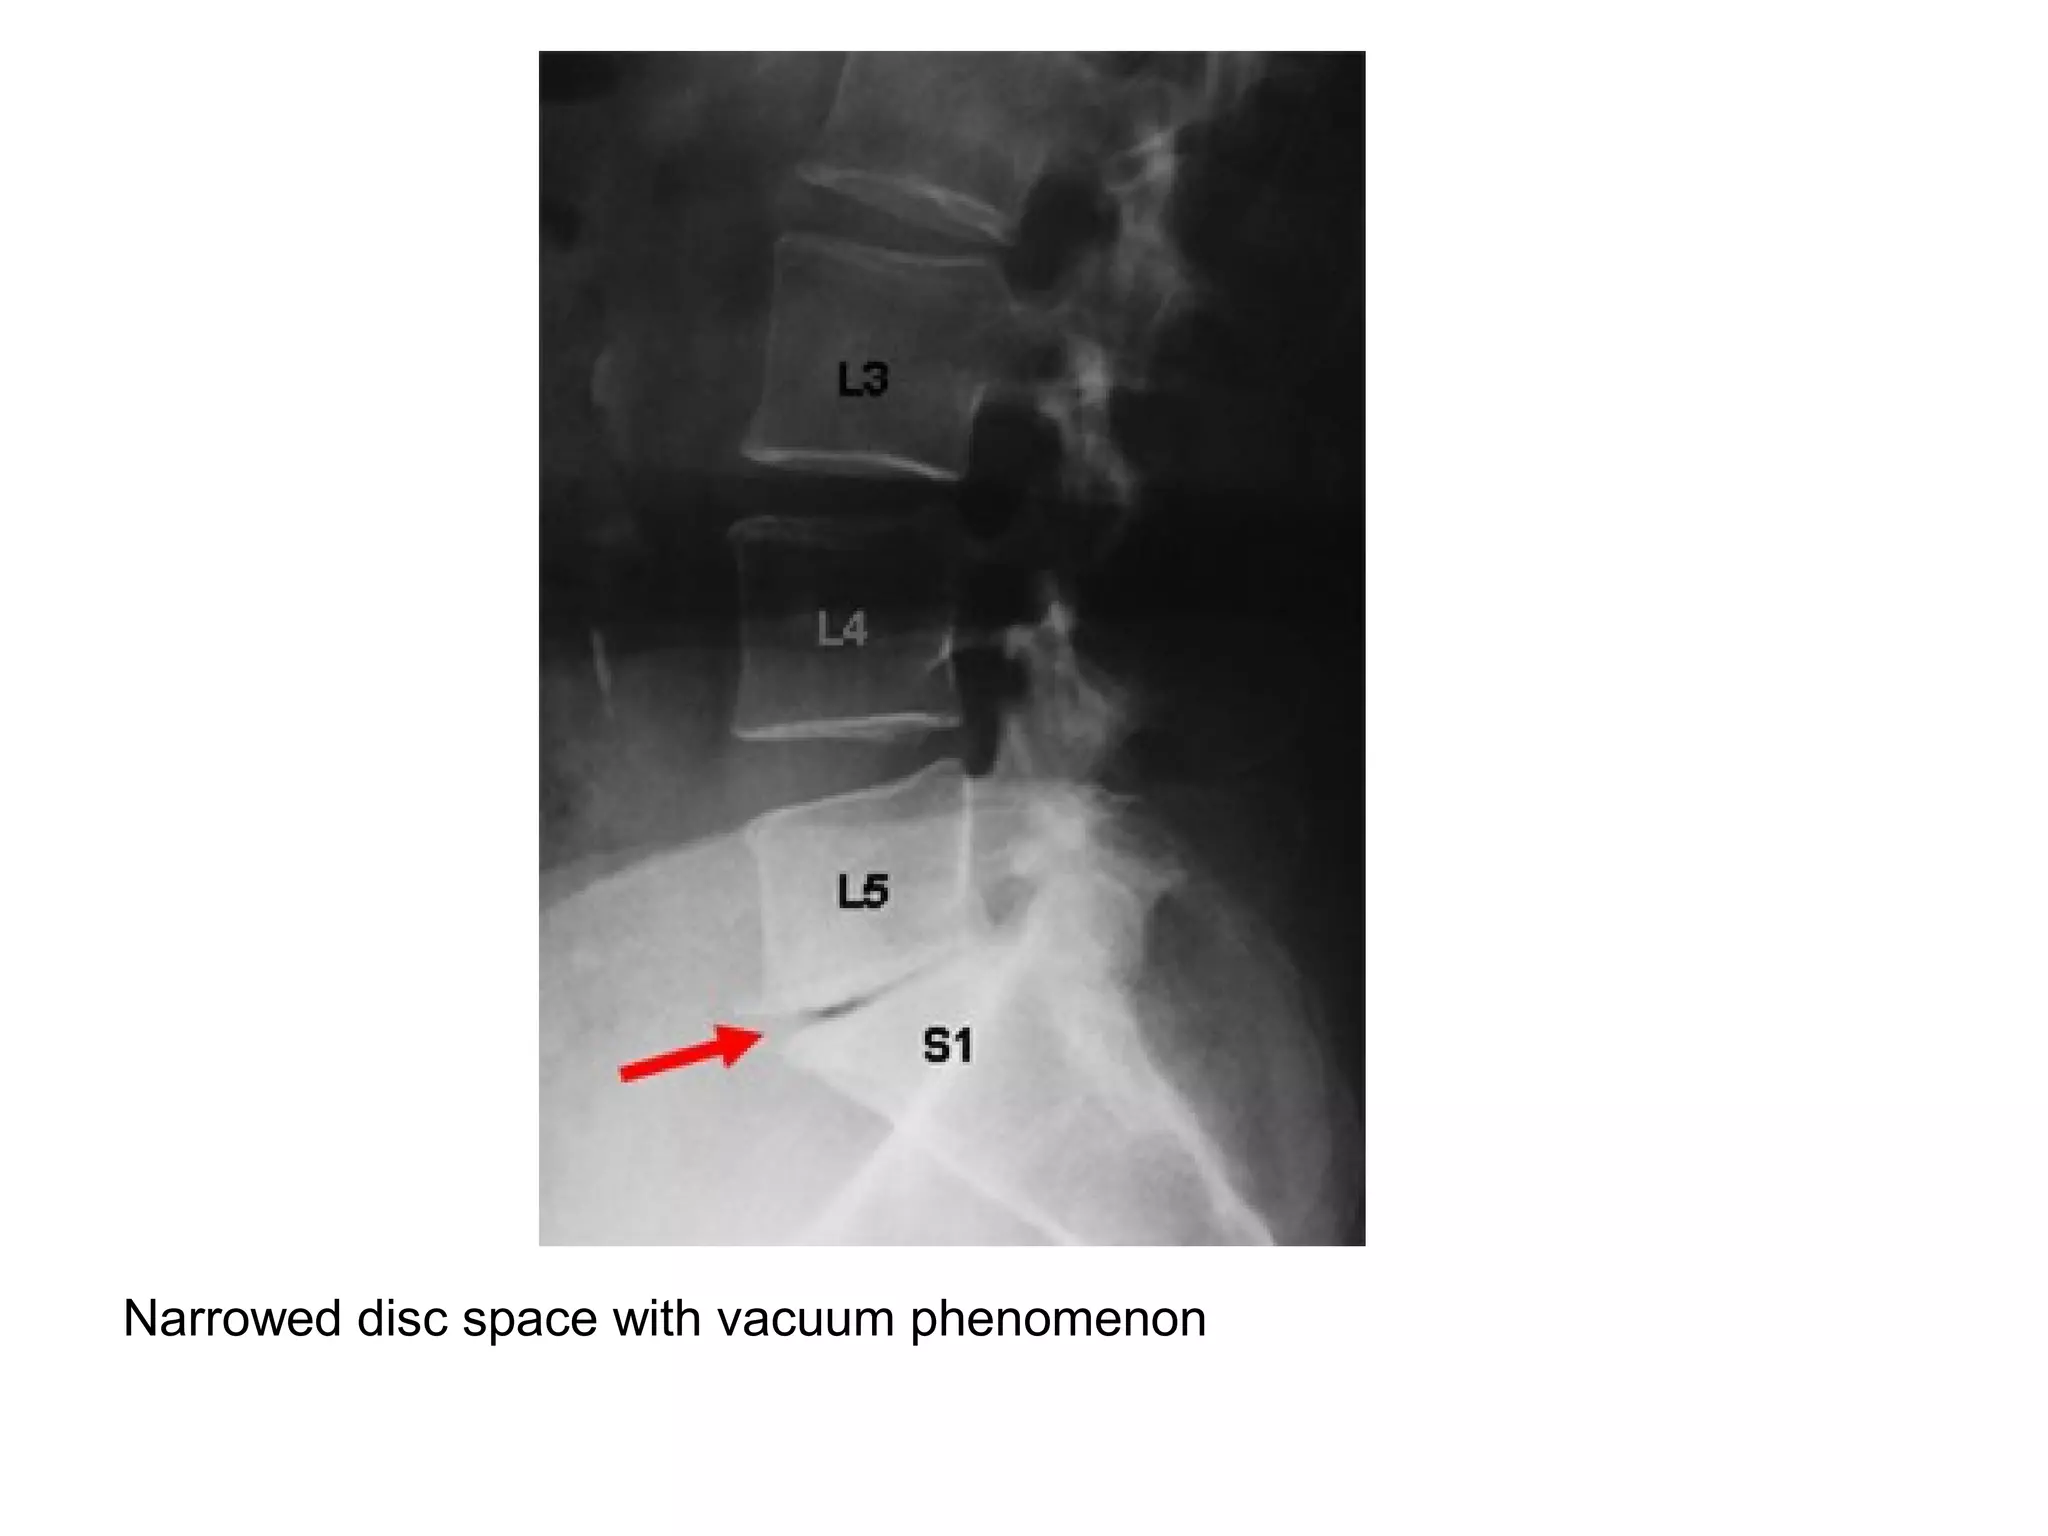

1-Plain Radiography :

-Disk space narrowing

-Vacuum phenomenon in disk space (gas in the

intervertebral disc) , pathognomonic for

degenerative disease

-Endplate osteophytes and sclerosis

Narrowed disc space with vacuum phenomenon